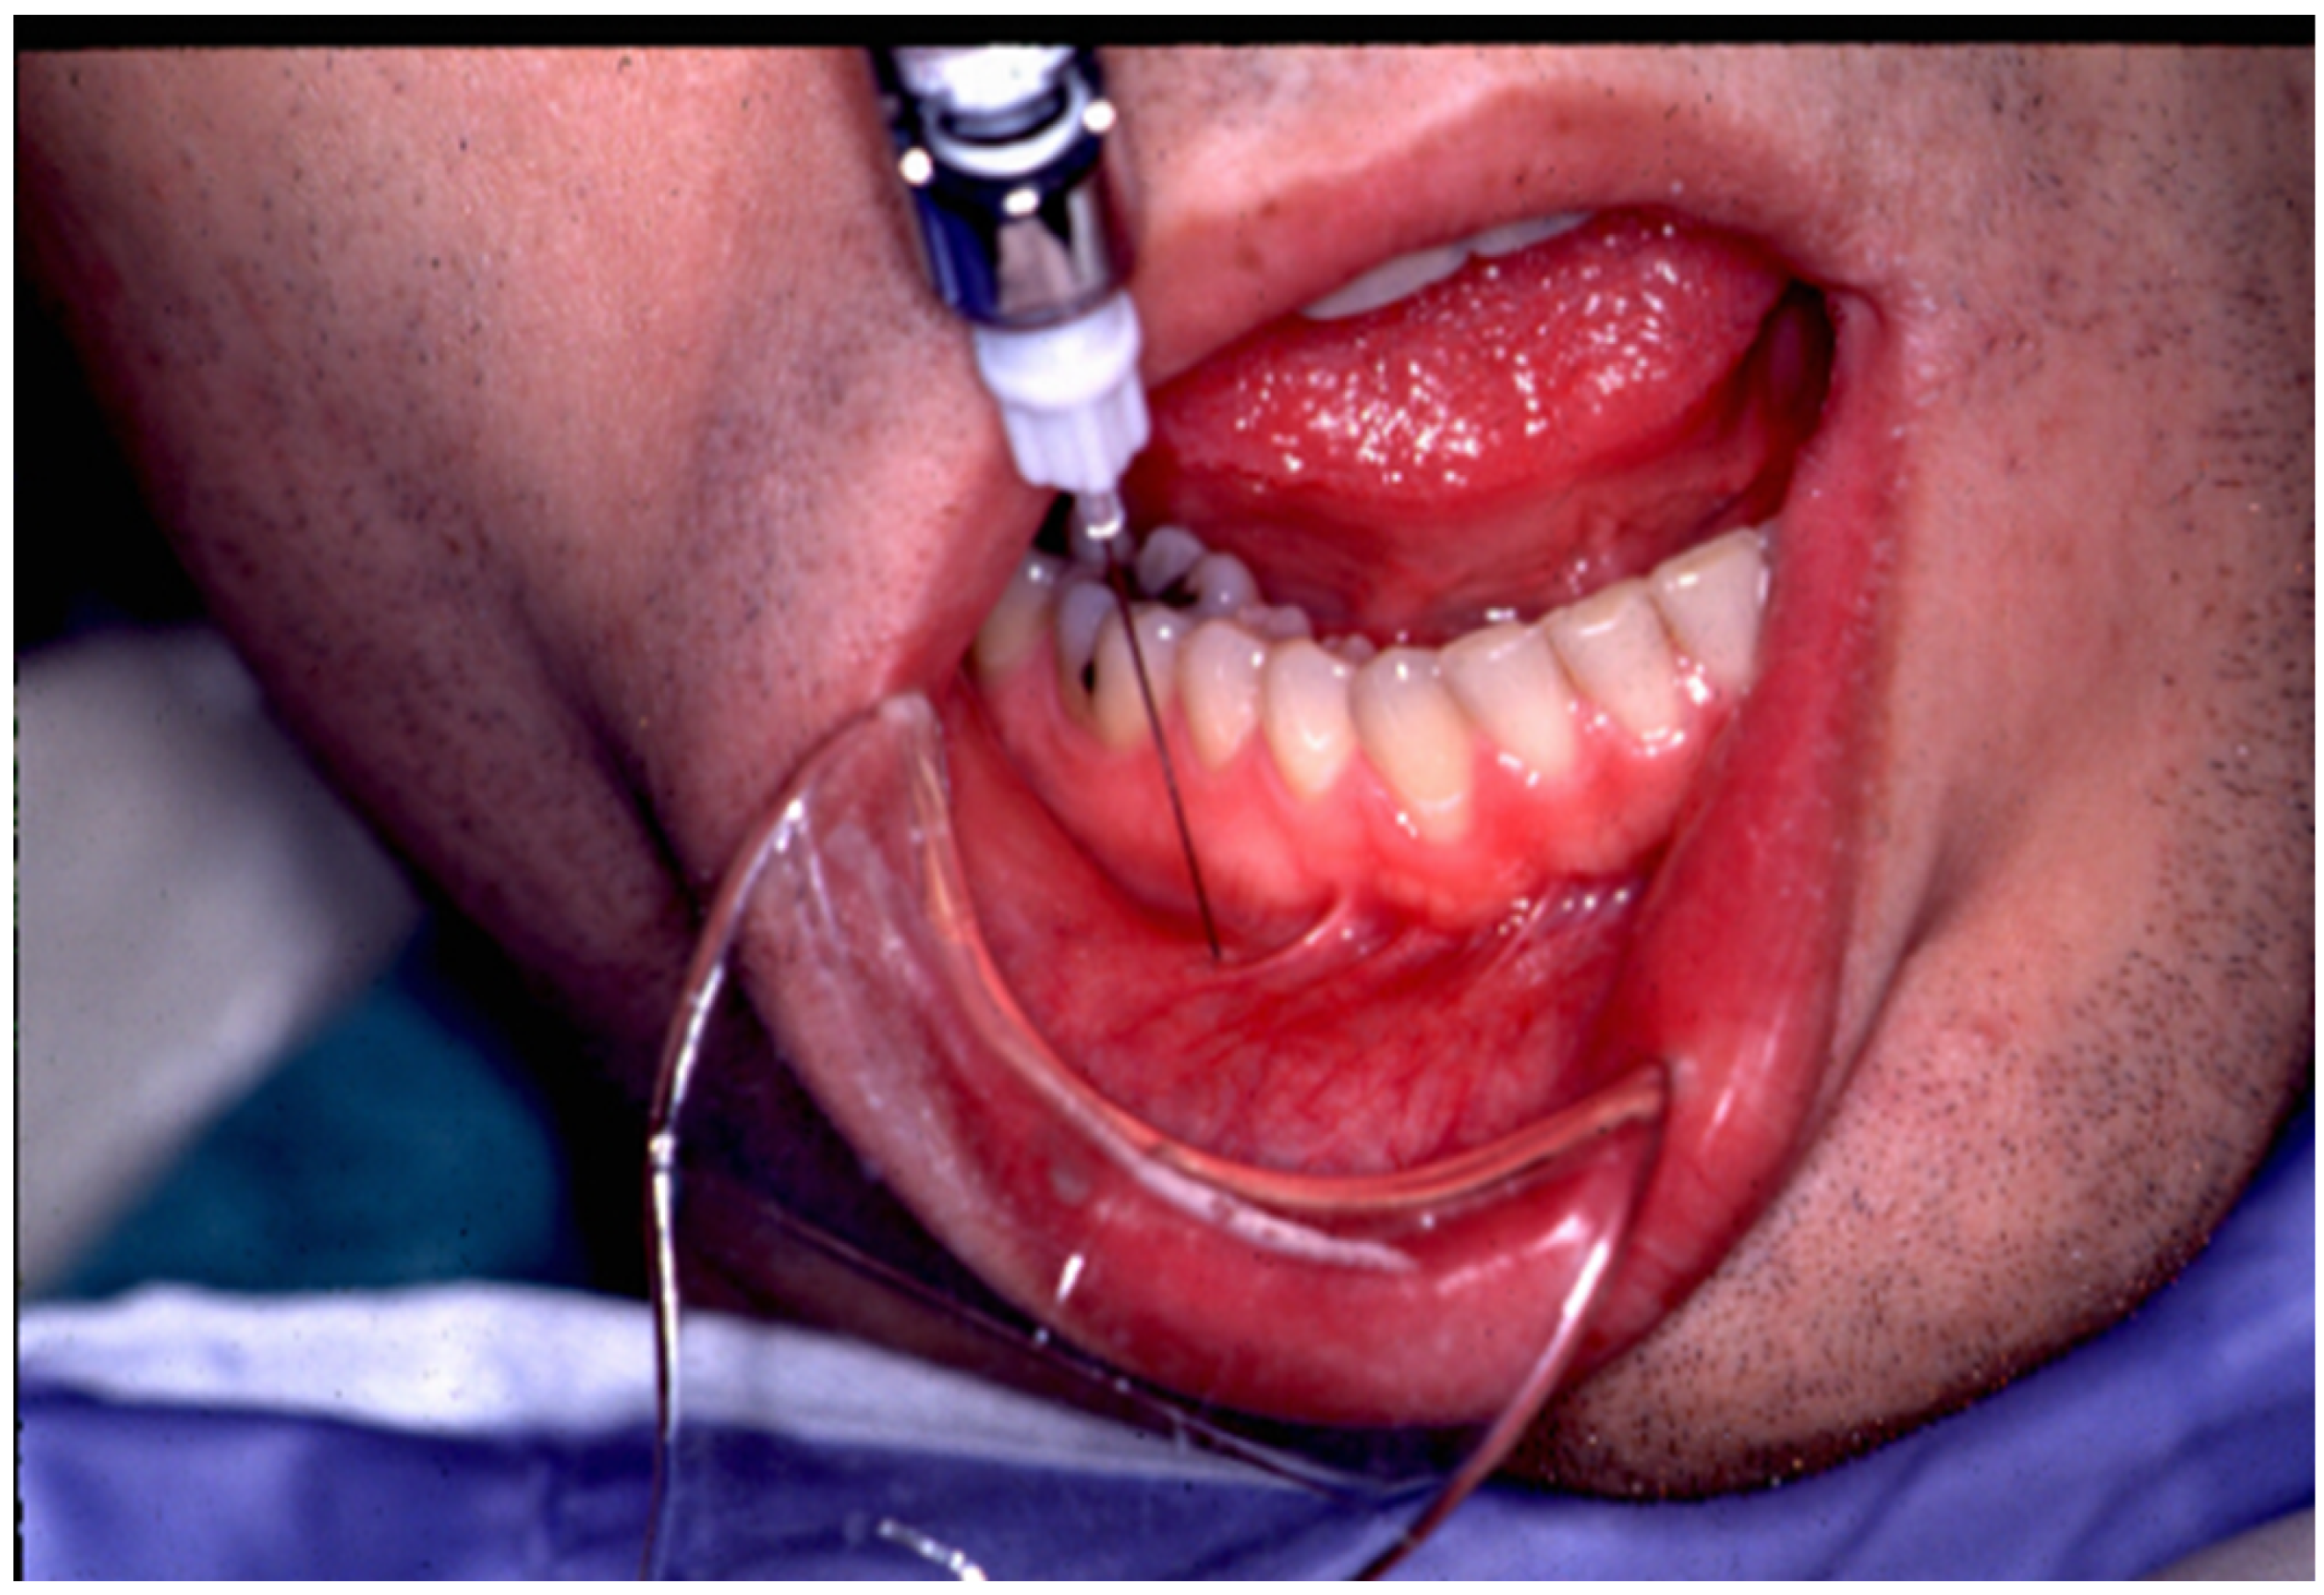

The lower lip on the injection side is retracted gently and the foramen is then identified using a dental syringe and needle or directly with the tuberculin syringe and 30 gauge needle. Lidocaine 1% plain may be injected prior to the BTX-A, depending on the patient’s preference. The 0.4 cc of BTX-A is injected at a 45–60-degree angle to the mandible, and the needle is initially advanced 2–3 mm, at which point, it usually contacts the bone of the mandible. Once the foramen is located, the needle can be further advanced an additional 2 mm just beyond the opening of the mental foramen. The BTX-A is then injected slowly to avoid pain or potential nerve injury (see Figure 1). Even without prior local anesthetic, the patient will report paresthesia for a couple of hours, which is frequently welcomed by the patient.

Figure 1. The technique demonstrated is used to locate the mental foramen and deposit a small amount of local anesthetic followed by Botulinum toxin type A as a treatment for trigeminal neuralgia.